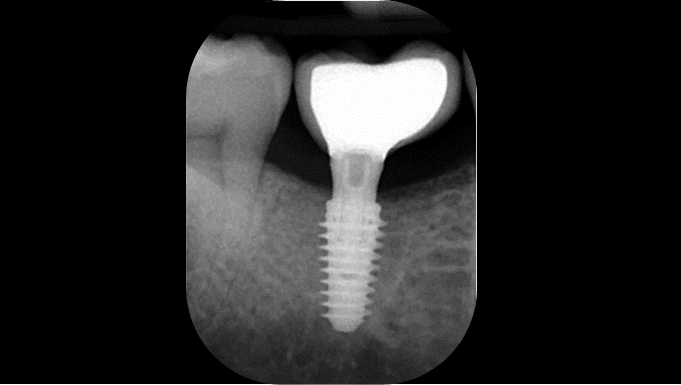

Clinical case: Delayed implant placement: sinus floor elevation by means of lateral

approach & implant placement with GBR

- Courtesy of Dr. Irfan Abas, Netherlands -

Clinical case: # 46 implant placement & GBR using i-Gen membrane for significant vertical resorption & mixed bone defect

- Courtesy of Dr. Iulian Filipov, Romania -